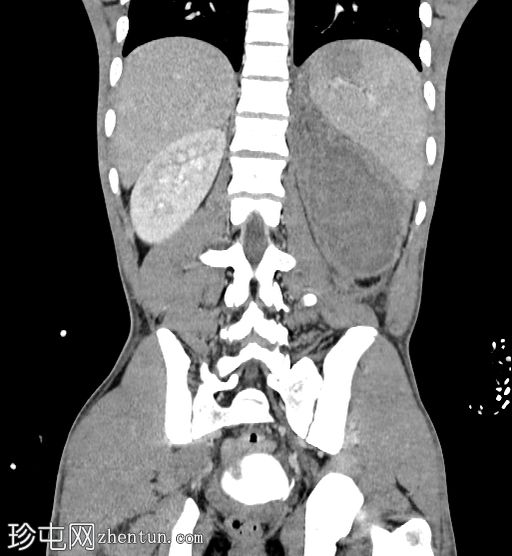

冠状位增强扫描(门静脉期)

左肾包膜下(毗邻肾后包膜)可见一相对高密度、无强化的积液(平扫时HU=70),包绕左肾。

左肾受巨大血肿压迫;但可见肾实质强化正常,造影剂排泄至集合系统。未见造影剂外渗。

III级肾损伤的特征(撕裂伤>1厘米,未累及集合系统,血肿局限于肾周筋膜内)